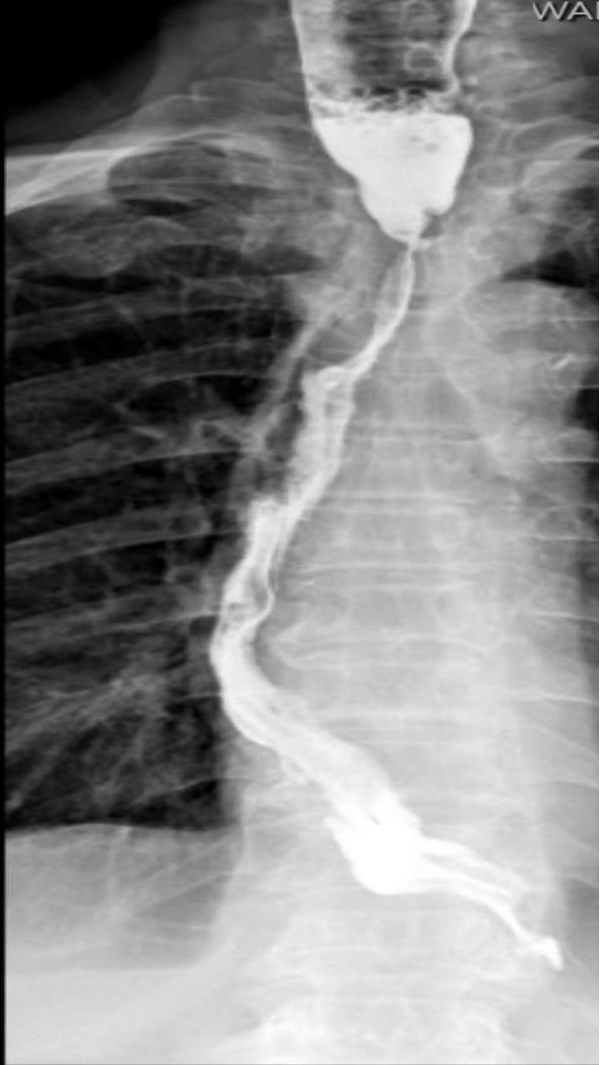

扩张前食管吻合口明显狭窄

X线透视下球囊扩张中

扩张后明显通畅